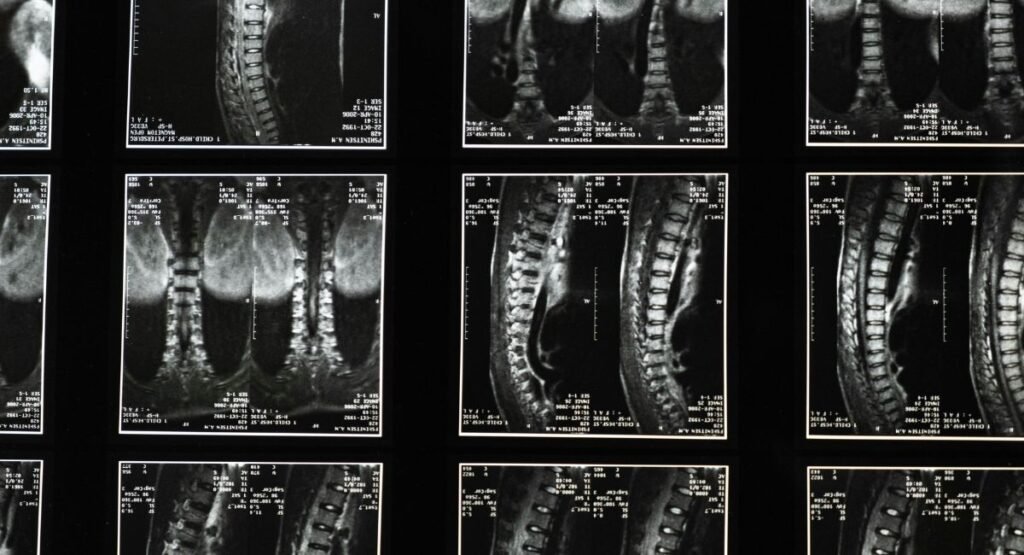

Some spinal abnormalities can produce back pain when I breathe in. For example, Disc prolapse, arthritis, or impingement of the nerve in the thoracic spine can lead to pain that worsens with activity or deep breathing.

Spinal pain in the back when I breathe in may also be felt to radiate out around the rib cage or into the front of the chest. This is because nerves in the thoracic region of the spine are connected to therib684.

If your pain persists despite resting and is associated with numbness or weakness, see a doctor.